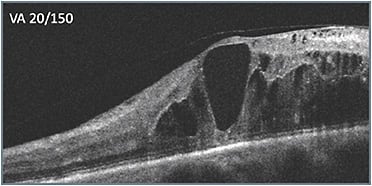

A 54-year-old female presented after having been treated by another physician with approximately 8 treatments for nonproliferative diabetic retinopathy (NPDR) and reduced vision (20/40). Leakage was present on the previously obtained initial ultra-widefield angiography. The previously obtained initial OCT scans (A) showed cystic fluid but intact retinal layer integrity, with the exception of some attenuation of the outer retinal layers, and only 1 noticeable hyperreflective focus nasally. Edema persisted and therapy was switched. After 2 treatments with the second therapy, vision improved slightly to 20/30 and edema improved (B).

Unfortunately, the patient was unable to return for 10 weeks. When she did return, (C) her vision had worsened dramatically (20/150). In deciding what to do, the apparent progression of disease signs that had occurred over time (B & C) were considered. Retinal layer disorganization progressed, including what appeared to be signs of DRIL. More hyperreflective foci appeared as well, presumably indicating accumulation of exudate, including near the fovea. The decision was made to switch to a different class of therapy, which produced a favorable response (D). Vision improved from 20/150 to 20/60, and the retinal anatomy appeared as intact as it had been during the course of treatment.